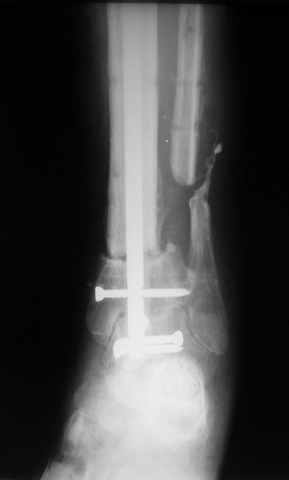

В случае гладкого заживления раны, при условии положительного решения вопроса с металлом, планируем перемонтаж аппарата Илизарова, дополнительную резекцию дистального отломка, выведение полокости голеностопного сустава в правильное положение (см. боковую Р-грамму), одномоментно остеотомия большеберцовой кости. После восстановления длинны голени, по всей видимости, артродез голеностопного сустава.

Рентгенограммы прилагаются. Фото местного статуса выложу в ближайшее время.

Мы обычно не фиксируем малоберцовую кость. Просто стараемся сопоставить ее концы за счет хорошей репозиции. В представленном случае имеется некоторое смещение дистальных фрагментов кнаружи, и, как мне кажется, ротация их вместе со стопой кнутри (ротация хорошо заметна на прямом снимке по форме таранной кости и на боковом по соотношению отломков малоберцовой). Если это действительно так, то это несложно сейчас постепенно устранить в аппарате. И тогда концы малоберцовой кости будут находиться поближе друг к другу.